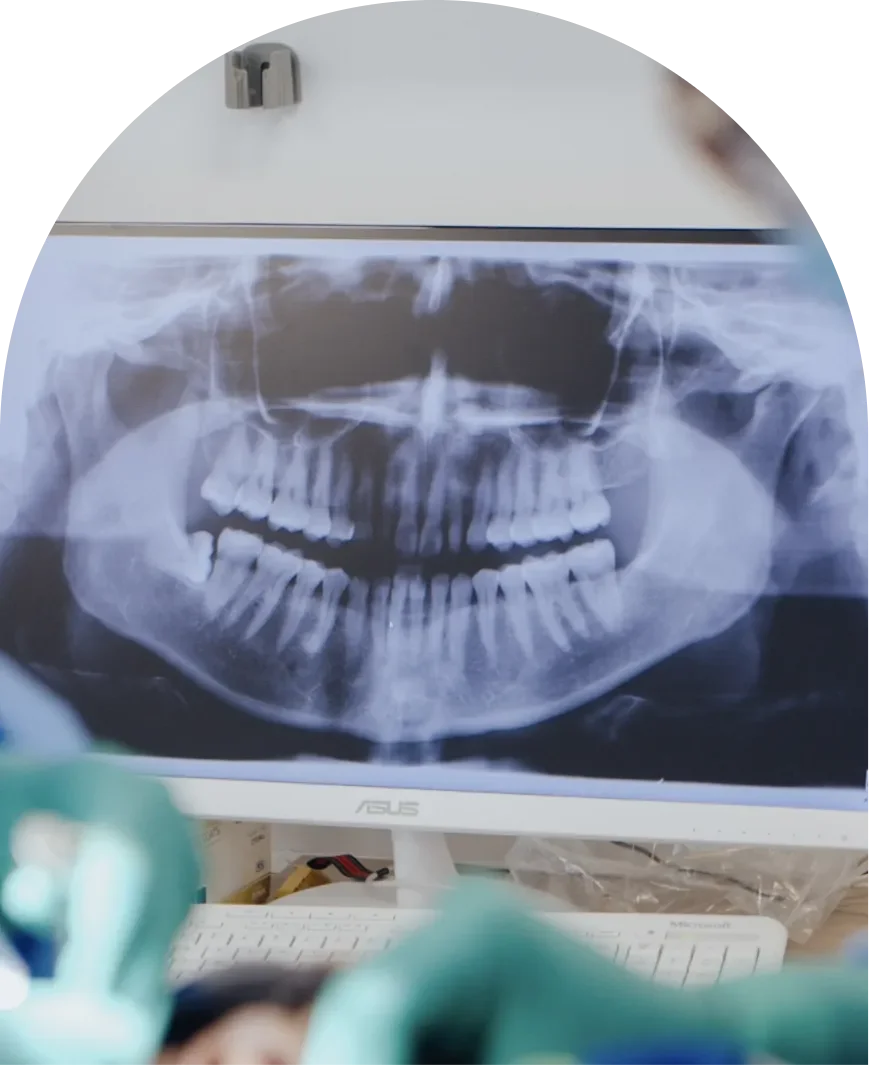

• Your initial consultation is essential for us to understand your oral health condition and diagnostics. We’ll take detailed 3D imaging of your mouth and determine whether extraction is necessary. If deemed necessary, we will take the time to discuss your condition, offer a personalised treatment plan, and all other relevant details to ensure you feel confident in making an informed decision.